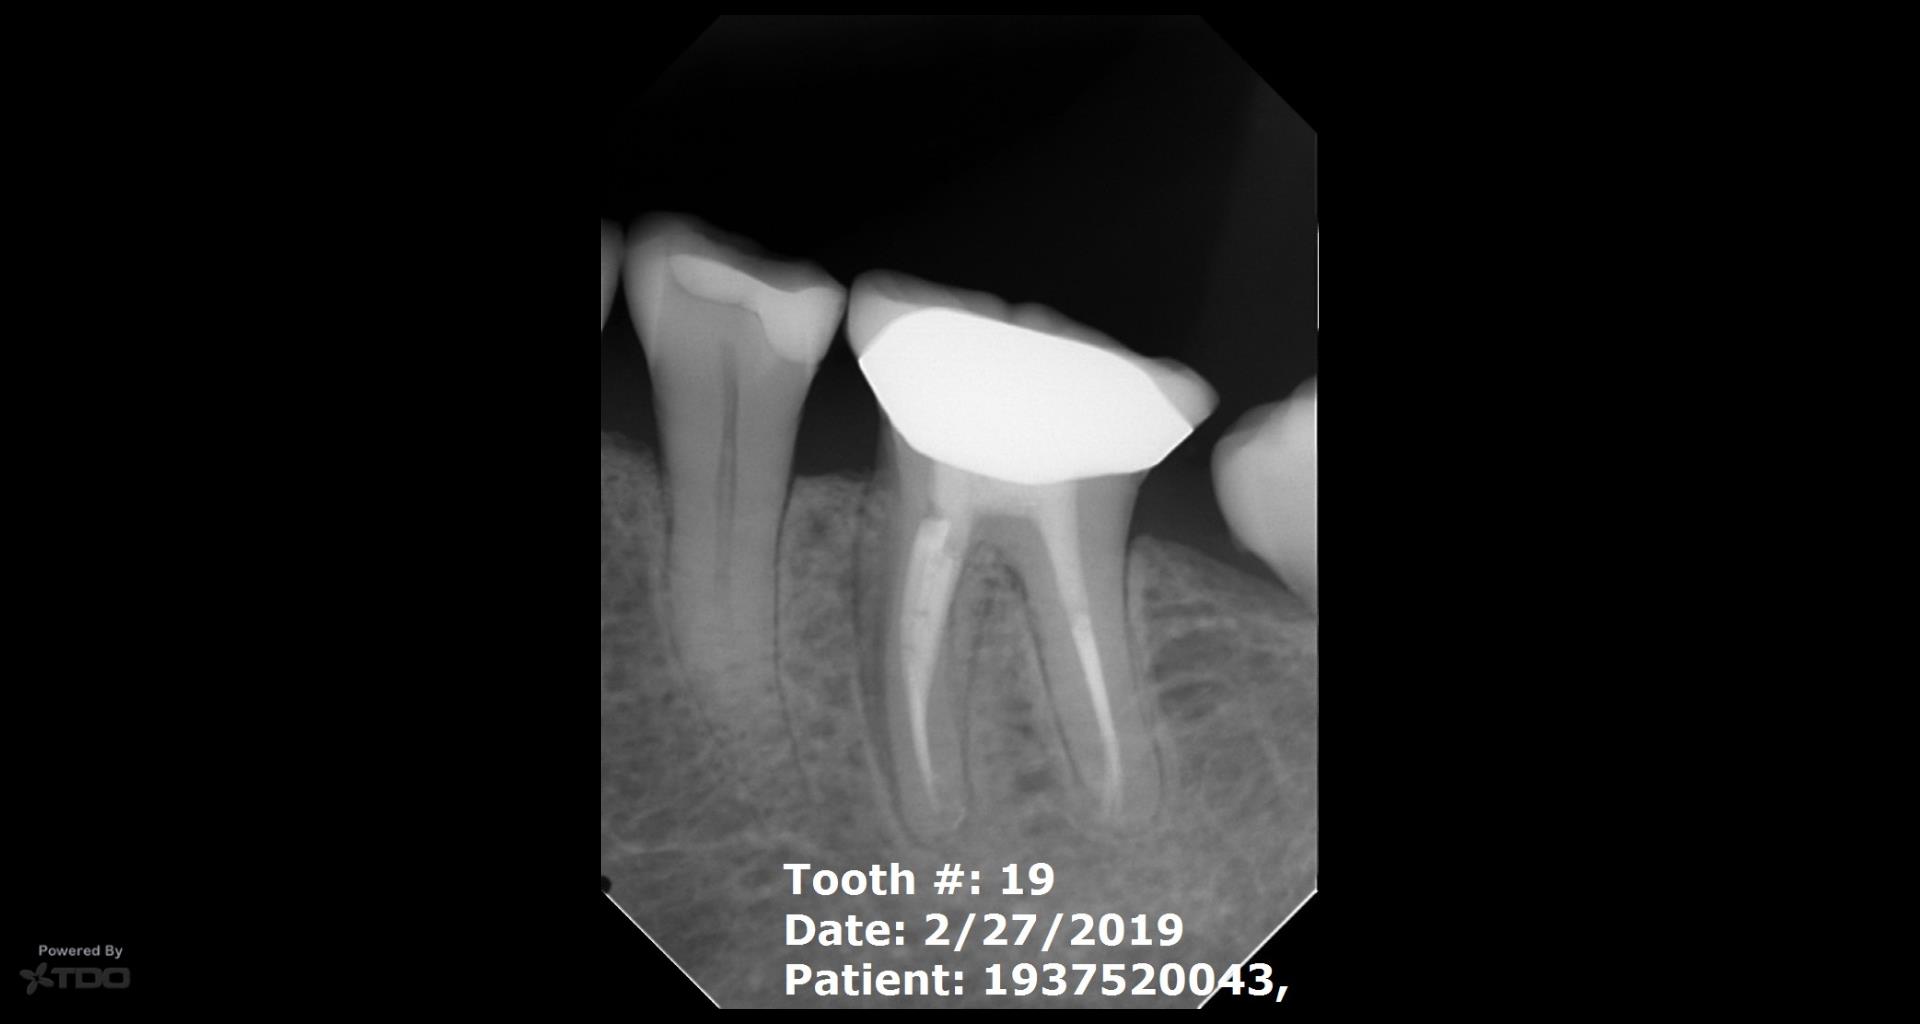

OK biofilm mavens…….I am ready to photograph the “Riccucci-style” processing of the apical distal root (#3)….. what do people think this will show? The same results Riccucci gets? Think before you answer….. gbc